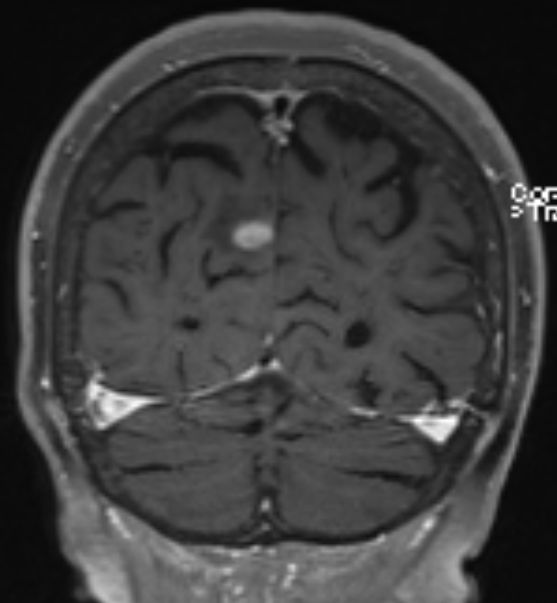

84-jährige Frau, die vor 3 1/2 Jahren einen 35 mm großen derben

Rektumpolypen entwickelte. Die submuköse Exzision ergab ein malignes Melanom

mit Infiltration der tiefen Muskulatur und Ummauerung größerer Gefäße. BRAF+.

Vor 2 Jahren Rektumschleimhau-Rezidiv und Metastase rechts pararektal:

anteriore Rektumresektion. Vor 4 Monaten Lungenmetastase und singuläre

Hirnmetastase re occipital. Dabrafinib + Trametinib nach 2 Zyklen wegen

Hepatotoxizität und Hautausschlag abgebrochen. Jetzt: RT der Hirnmetastase

und des pararektalen Tumors. |